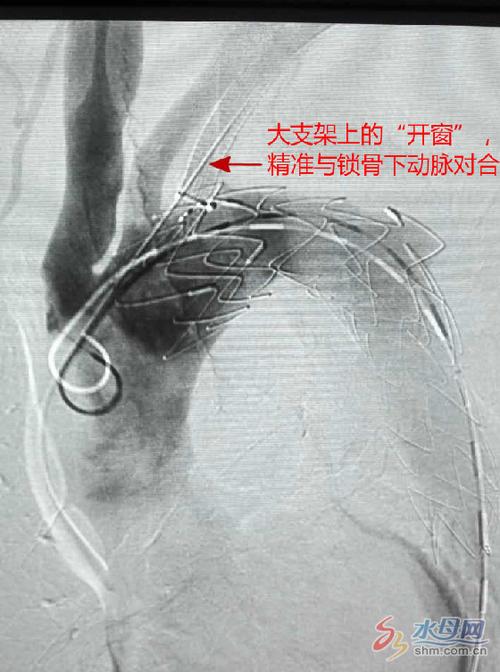

大支架上的"开窗"精准与锁骨下动脉对合

见右侧椎动脉向左侧椎动脉盗血 再行左侧锁骨下支架置入,下图为支架

神经内科独立完成锁骨下动脉支架置入手术一例

放置支架后开通已闭塞的左侧锁骨下动脉,血流恢复.

66岁男性左锁骨下动脉狭窄,2017年12月从蛇口慕名来光明新区医疗集团